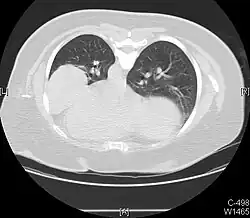

Foreign body aspiration

Foreign body aspiration is a major cause of death in young children due to their underdeveloped swallowing coordination. Young children most commonly ingest toys, coins, or food.[21] On chest x-ray, the most frequent sign is air trapping that can lead to a mediastinal shift. Atelectasis and pneumothorax may also occur in the setting of foreign body aspiration. The diagnosis is made in conjunction with clinical symptoms and confirmed and treated with bronchoscopy.[22]